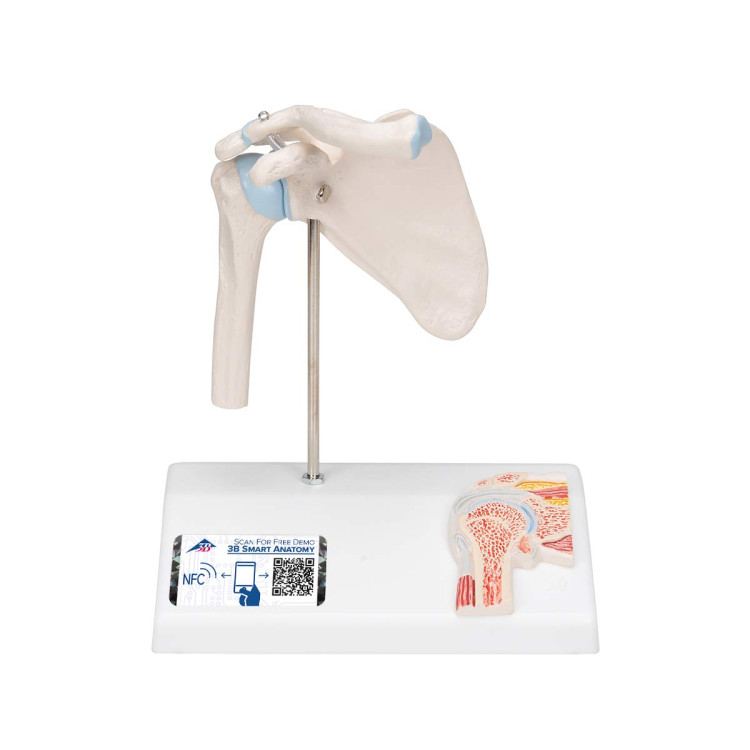

A86/1 Mini Shoulder Joint Model with Cross Section

A86/1 Mini Shoulder Joint Model with Cross Section

Το μοντέλο mini shoulder joint έχει μειωθεί στο μισό του μέγεθος, έχει διατηρήσει όμως όλες τις λεπτομέρειες της λειτουργίας του ώμου. Εκτός από τις εξωτερικές ανατομικές δομές της άρθρωσης, ο ιατρός ή ο επαγγελματίας υγείας έχει πλέον τη δυνατότητα να εξηγήσει τι συμβαίνει στο εσωτερικό της άρθρωσης.

Βάρος: περίπου 0,25 kg. Διαστάσεις: 12x14x16cm